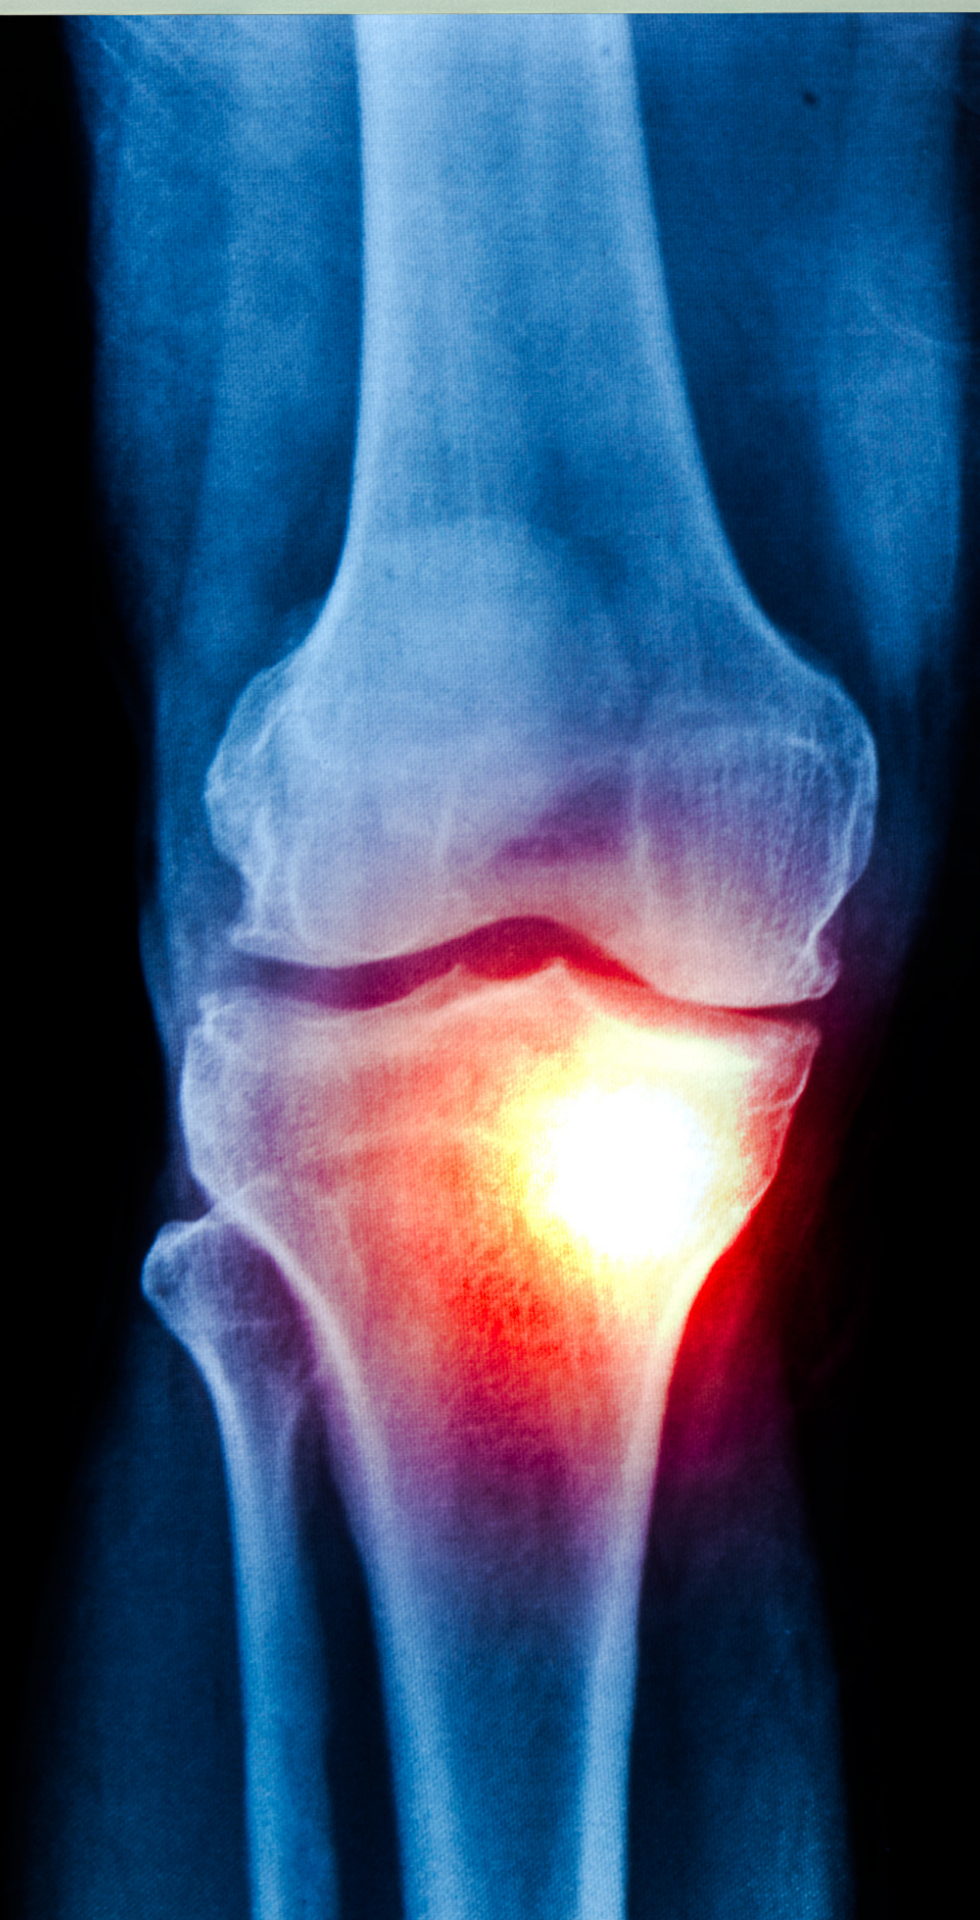

¿Qué es la osteoartritis y a quién afecta?

Ocurre cuando el cartílago que protege las articulaciones se desgasta, generando fricción entre los huesos.

Es más frecuente a partir de los 50 años, aunque puede aparecer antes si existen factores que la favorecen.

Lo más importante es no ignorar el dolor cuando se vuelve constante. Consultar a tiempo permite identificar el grado de desgaste y evitar que el problema avance.